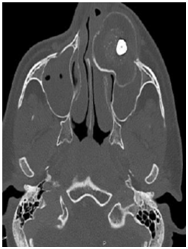

Panoramic Radiographic was obtained shows a large unilocular radiolucency on the left side of the maxilla, extending from tooth #22 to #26. Unerupted tooth #23 was present inside the lesion. Computed Tomography (Figure 2) (Figure 3) of facial bone was obtained shows well circumscribed unilocular radiolucency and radiolucency involves the crown of unerupted tooth #23. Based on the history and clinical features and radiographic evaluation dentigerous cyst and adenomatoid odontogenic tumour was made as provisional diagnosis. Other strictly radiolucent lesions worthy of consideration are keratocystic odontogenic tumor, ameloblastic fibroma, odontogenic myxoma, or central giant cell tumour as well as unicystic ameloblastoma which is common in this age.

Figure 3 Paranasal sinus computed tomography coronal view.

Panoramic Radiograph does give a comprehensive view of the lesion, but a multi-slice CT scan provides the extension of the lesion in all directions besides showing dental involvement, as in this case it revealed intracapsular presence of canine tooth which couldn't hence be saved. It also showed involvement of the maxillary sinus and aided in treatment planning. Quality and quantity of the scattered radiopaque foci can also be well appreciated on the CT scan. CT scan provides proper extensions of the AOT, reveals proximity to the vital structures which aid in the preoperative evaluation, provisional diagnosis, planning and execution of the surgical procedure.